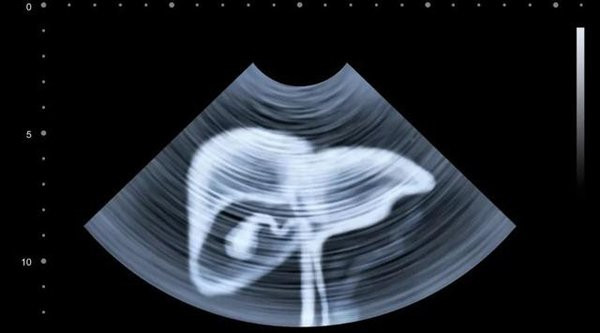

Do đó, để phát hiện ung thư gan và kịp thời chữa trị, chúng ta nên thường xuyên đến các cơ sở y tế khám và kiểm tra sức khỏe.

- Khám sức khỏe định kỳ: ung thư gan chỉ được chữa trị khi phát hiện kịp thời, vì vậy chúng ta cần đi khám sức khỏe thường xuyên để đảm bảo mình có một cơ thể khỏe mạnh.